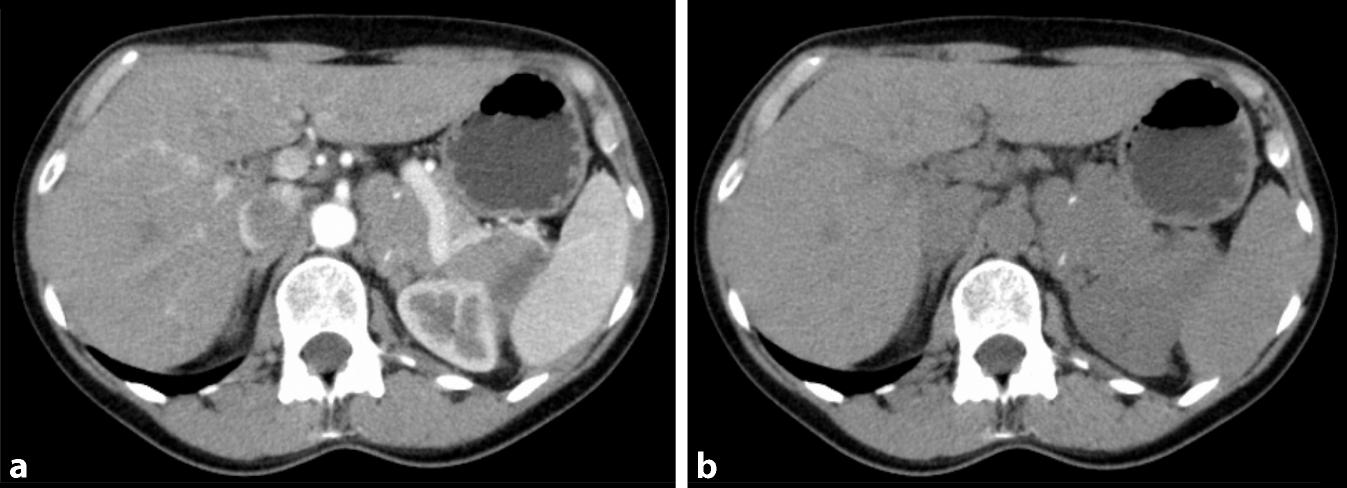

Bildgebung

Abb. 1

Computertomographie (nativ) eines Nebennierenadenoms rechts